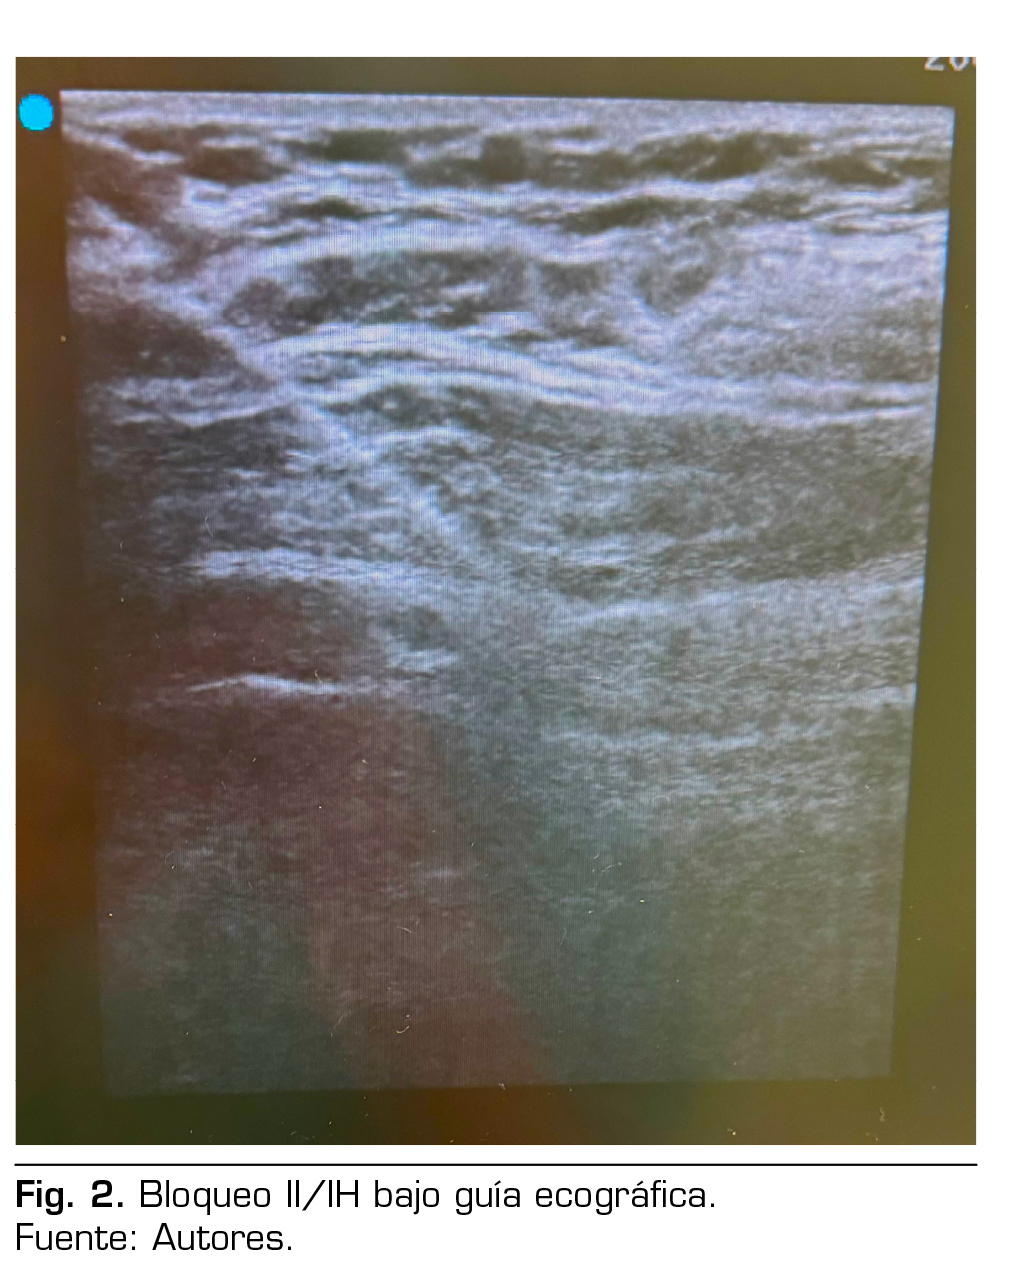

Figura 1